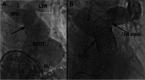

There is a growing appreciation for the adverse long-term impact of right-sided valvular dysfunction in patients with congenital heart disease. Although right-sided valvular stenosis and/or regurgitation is often better tolerated than left-sided valvular dysfunction in the short and intermediate term, the long-term consequences are numerous and include, but are not limited to, arrhythmias, heart failure, and multi-organ dysfunction. Surgical right-sided valve interventions have been performed for many decades, but the comorbidities associated with multiple surgeries are a concern. Transcatheter right-sided valve replacement is safe and effective and is being performed at an increasing number of centers around the world. It offers an alternative to traditional surgical techniques and may potentially alter the decision making process whereby valvular replacement is performed prior to the development of long-term sequelae of right-sided valvular dysfunction.